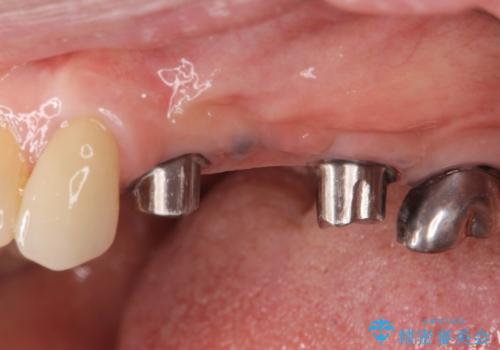

複数の奥歯の欠損 インプラントによる咬合機能回復

- 多数の奥歯を失い、咬合機能の回復を希望され来院されました。

このような場合、入れ歯、もしくはインプラントによる咬合機能の回復のご提案となります。

「より今後しっかり噛めるようになりたい。」というご希望を踏まえて、インプラントによる治療計画を立案します。

- 105.6万円(インプラント×2・チタンカスタムアバットメント×2・ジルコニアクラウン×3・仮歯×3)費用は治療当時の料金となります